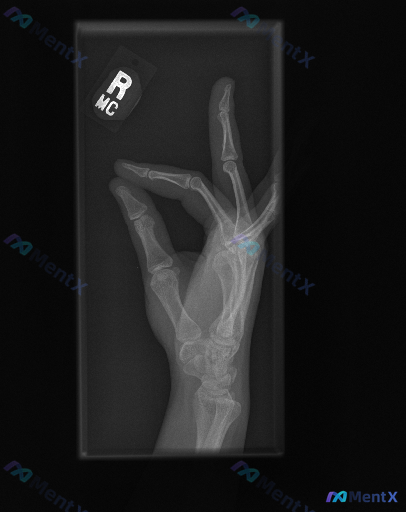

右手侧位片的这个病灶,真的只是“扭伤”这么简单吗?

整理到一份右手侧位X光片的影像资料,结合报告看属于典型的骨科急症,但先只看描述,大家第一眼思路会落在哪里? 先给基础影像表现: - 成年患者(骨骺已闭合) - 拇指近节指骨基底部骨皮质不连续,可见透亮骨折线,累及关节面,伴移位 - 其余掌骨、指骨、腕骨未见明确骨折征象 - 拇指掌指关节周围软组织密度...